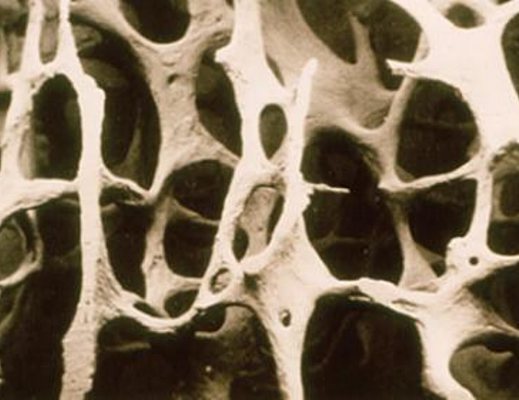

L’osteoporosi –ha spiegato il dr. Antonio Toro- è una malattia sistemica dello scheletro caratterizzata da una ridotta massa ossea e da alterazioni qualitative che si accompagnano ad aumento del rischio frattura.

L’indagine densitometrica (MOC) consente oggi di misurare in modo abbastanza accurato e preciso la massa ossea ed in particolare la sua densità minerale”.